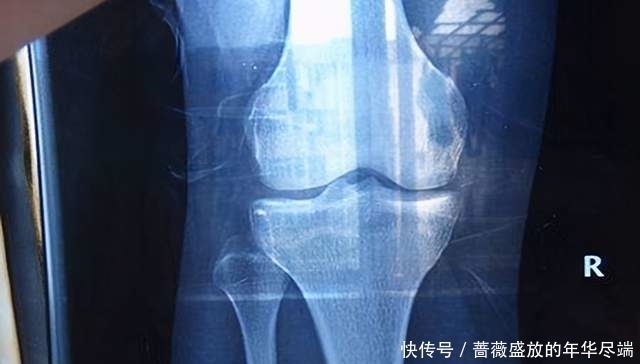

因为人的骨骼发育需要钙,而性早熟的孩子钙储备并不多,并且性早熟会加速骨骼骨骺线闭合,所以孩子会暂停长个。